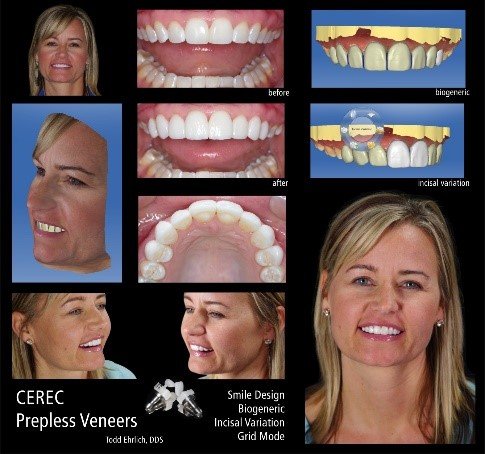

Case Study 2: Digital Workflow for Porcelain Veneers

Patient Profile:

- 42-year-old male

- Chief complaint: “I want to close my gap and improve the color of my teeth”

- 2.5mm midline diastema with mild tetracycline staining

- Previous orthodontic treatment with relapse

- Moderate incisal wear from bruxism

Diagnostic Process:

- Comprehensive digital records:

- Full-face and intraoral photographs

- Intraoral scan (iTero Element 5D)

- Digital smile design analysis

- T-Scan occlusal analysis

- Digital treatment planning:

- 3D virtual wax-up

- Preparation depth analysis

- Material selection simulation

- Occlusal scheme verification

Treatment Protocol:

- Minimally invasive preparation guided by 3D-printed reduction guide:

- 0.3mm facial reduction

- 0.5mm incisal reduction

- Supragingival margin placement

- Digital impression and provisional phase:

- Immediate provisionals milled from pre-approved design

- Two-week functional and aesthetic assessment period

- Final restoration fabrication:

- Material selected: lithium disilicate (IPS e.max)

- Staining and glazing for enhanced characterization

- Thickness: 0.5mm facial, 1.0mm incisal

- Adhesive cementation protocol:

- Try-in with glycerin-based paste

- 5% hydrofluoric acid etch (20 seconds)

- Silane application (60 seconds)

- Adhesive resin application (no light cure)

- Light-cured resin cement (A1 shade)

Three-Year Follow-up:

- Complete diastema closure maintained

- No ceramic fractures

- Minor occlusal adjustment needed at 2-year recall

- Excellent margin integrity and color stability

CEREC Smile Design   | Dentsply Sirona | Chairside integration, immediate visualization | CEREC ecosystem | Easy | Included with CEREC |